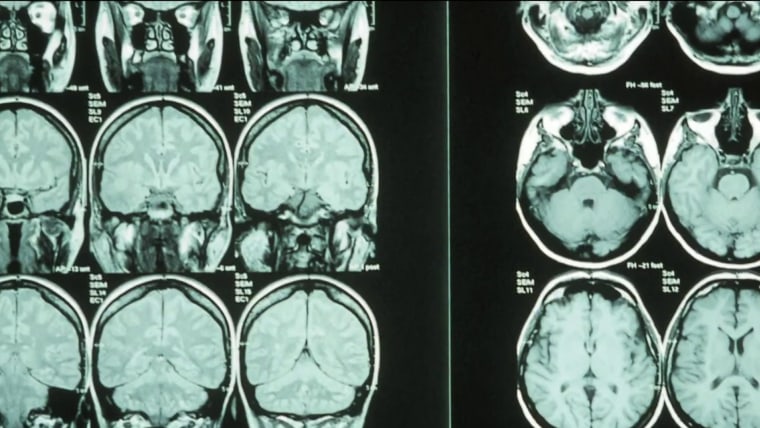

A new study out of the U.K. lays out how thumbs helped shape brain development in humans and other primates. Scientists found a link between thumb size and the size of the neocortex which is involved in higher-order brain functions, which they say suggests that thumbs are linked to "thinking and not movement."